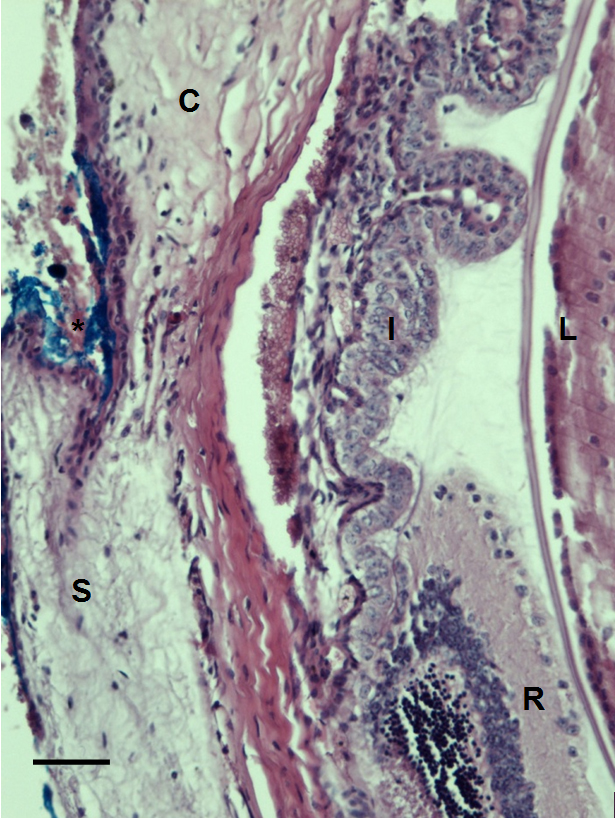

Figure 6. Histological section of C57BL/6 mouse eye imaged with our multiphoton microscope. Eye structures appear normal after imaging.

No distortion or photocoagulation is noted in the tissues near the drainage angle of the eye. Blue dye was used to mark the

orientation of the eye before enucleation (*). S=sclera. R=retina. I=iris. C=cornea. L=lens. The scale bar represents 50 µm.